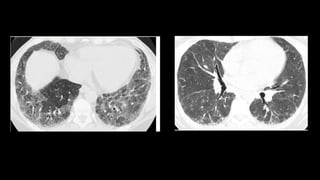

Fibrotic NSIP

• Ground-glass opacity or reticulation

• “without“ honeycombing

• subpleural and basal lung

• subpleural sparing